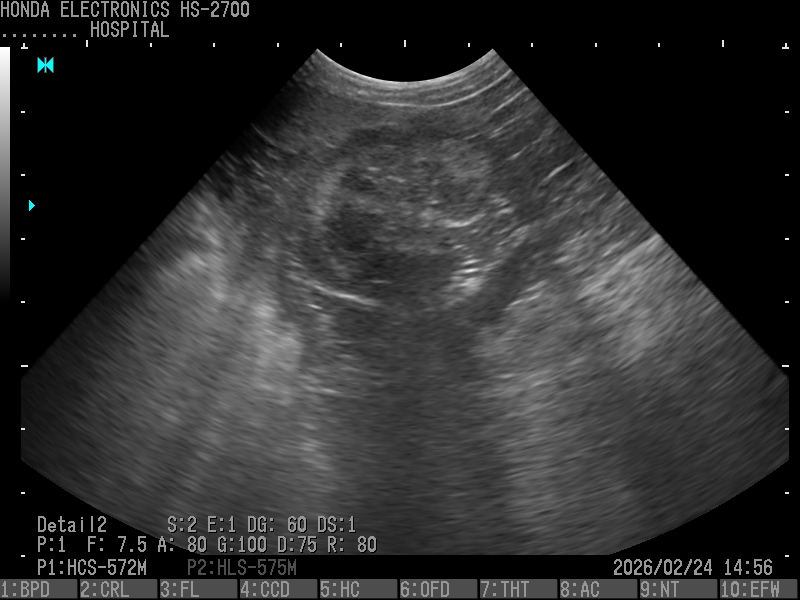

1.胆嚢、肝臓(パピヨン・10歳)

プローブ:HCS-572M

H-res:Detail2